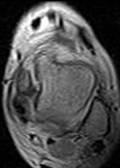

При МР-томографии интенсивность сигнала задней малоберцово-таранной связки повышена на Т2 ВИ, контуры прерывисты.

|

| Рис 2. Аксиальная и коронарная плоскости сканирования. Т2 ВИ. Стрелкой показан полный разрыв задней малоберцово-таранной связки. В коронарной плоскости (б) можно лишь предположить наличие повреждения, а на аксиальной (а) это полностью подтверждено. | ||||

| Рис 3. Саггитальная плоскость сканирования. Т2 и Т1 ВИ. Стрелками указаны повышенное скопление жидкости в переднем и заднем заворотах, в полости суставов – большеберцово-таранном и таранно-пяточном. Повреждение каких-либо связок можно лишь предположить. |